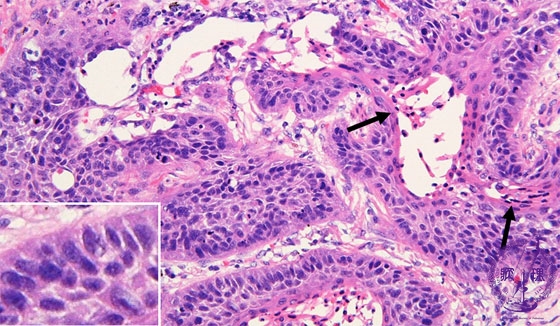

- ★(17)Non-small cell lung carcinoma(squamous cell carcinoma)

Microscopic view (HE stain, high power view): Squamous cell carcinoma of lung. Tumor cells proliferate in sheets while maintaining intercellular bridges (left lower inset). The cytoplasm is eosinophilic and elongated, features indicative of keratinization (arrow).